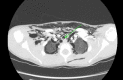

Tracheal lacerations in the paediatric population are not common; however, they can be life-threatening. Prompt diagnosis and management are essential for a good prognosis. Here, we present the case of a nine-year-old boy who presented to the hospital following a bicycle handlebar injury with neck pain and subcutaneous emphysema of the anterior thorax and neck. Chest X-ray revealed pneumomediastinum and a small pneumothorax. A computed tomography scan revealed a posterior longitudinal laceration of the trachea, measuring 1.5 cm, located superior to the carina at T1/2. As the patient was clinically stable, did not require any supplemental oxygen, and the tear was smaller than 2 cm, conservative management with steroids and broad-spectrum antibiotics was implemented. The patient was transferred to a tertiary ENT centre in Glasgow for observation in the paediatric intensive care unit where he recovered uneventfully. A repeat cross-sectional imaging six days after the injury revealed successful healing of the laceration. Non-surgical management of a tracheobronchial injury can be an effective approach. This can be considered in the case of tears measuring <2 cm and in clinically stable patients. Imaging-based diagnosis in the case of patients with minor injuries who are improving with conservative treatment may be sufficient, and confirmation with bronchoscopy would be of questionable clinical value in such patients.